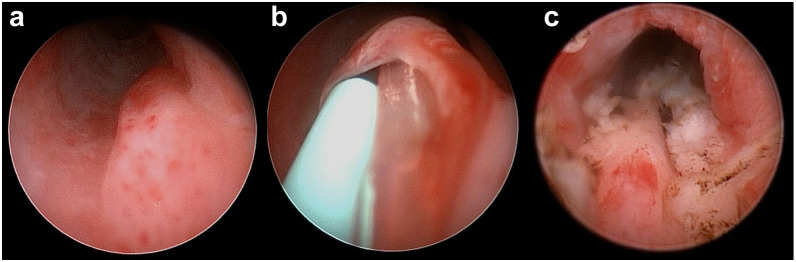

本研究的目的是报告4只母猫的临床表现、诊断评价和输尿管异位治疗结果。回顾了2016年至2021年间诊断为输尿管异位的猫的医疗记录。如果猫被确诊为外输尿管(3例)或内输尿管(1例)异位,并接受了膀胱内端侧神经输尿管造口术或膀胱镜下激光消融术的手术矫正。从医疗记录中获得的信息包括病史、信号、临床病理数据、影像学结果、治疗情况、术后并发症和长期临床随访。4只患有单侧异位输尿管的母猫均出现尿失禁(4/4),其中一半(2/4)还出现复发性尿路感染。治疗前诊断为外壁异位输尿管3例,内壁异位输尿管1例。相关性和新信息对三只外壁异位输尿管猫行膀胱内神经输尿管端侧造口术,对外壁异位输尿管猫行膀胱镜激光消融术。长期随访显示,异位输尿管治疗后无尿失禁复发或下尿路体征(中位随访1705天)。本研究表明,膀胱内输尿管端侧神经输尿管端侧造口术和膀胱镜下激光消融术是治疗猫单侧输尿管异位的有效且安全的长期治疗选择。

Case series summaryThe objective of this study was to report the clinical presentation, diagnostic evaluation and outcome of ectopic ureter treatment in four female cats. Medical records of cats diagnosed with ectopic ureter between 2016 and 2021 were reviewed. Cats were included if they had a confirmed diagnosis of an extramural (three cases) or intramural (one case) ectopic ureter and underwent either surgical correction using an intravesicular end-to-side neoureterocystostomy technique or cystoscopic laser ablation. Information obtained from the medical records included history, signalment, clinicopathological data, imaging findings, treatment performed, postoperative complications and long-term clinical follow-up. Four female cats with unilateral ectopic ureters were identified, all of which (4/4) presented with urinary incontinence, with half (2/4) also having recurrent urinary tract infections. Pre-treatment diagnostics revealed three cases of extramural and one case of intramural ectopic ureters.Relevance and novel informationSurgical correction was performed using intravesicular end-to-side neoureterocystostomy for the three cats with an extramural ectopic ureter and cystoscopic laser ablation for the cat with an intramural ectopic ureter. Long-term follow-up showed no recurrence of urinary incontinence or of lower urinary tract signs after ectopic ureter treatment (median follow-up 1705 days). This study demonstrates that both intravesicular end-to-side neoureterocystostomy and cystoscopic laser ablation are effective and safe long-term treatment options for cats with unilateral ectopic ureters.